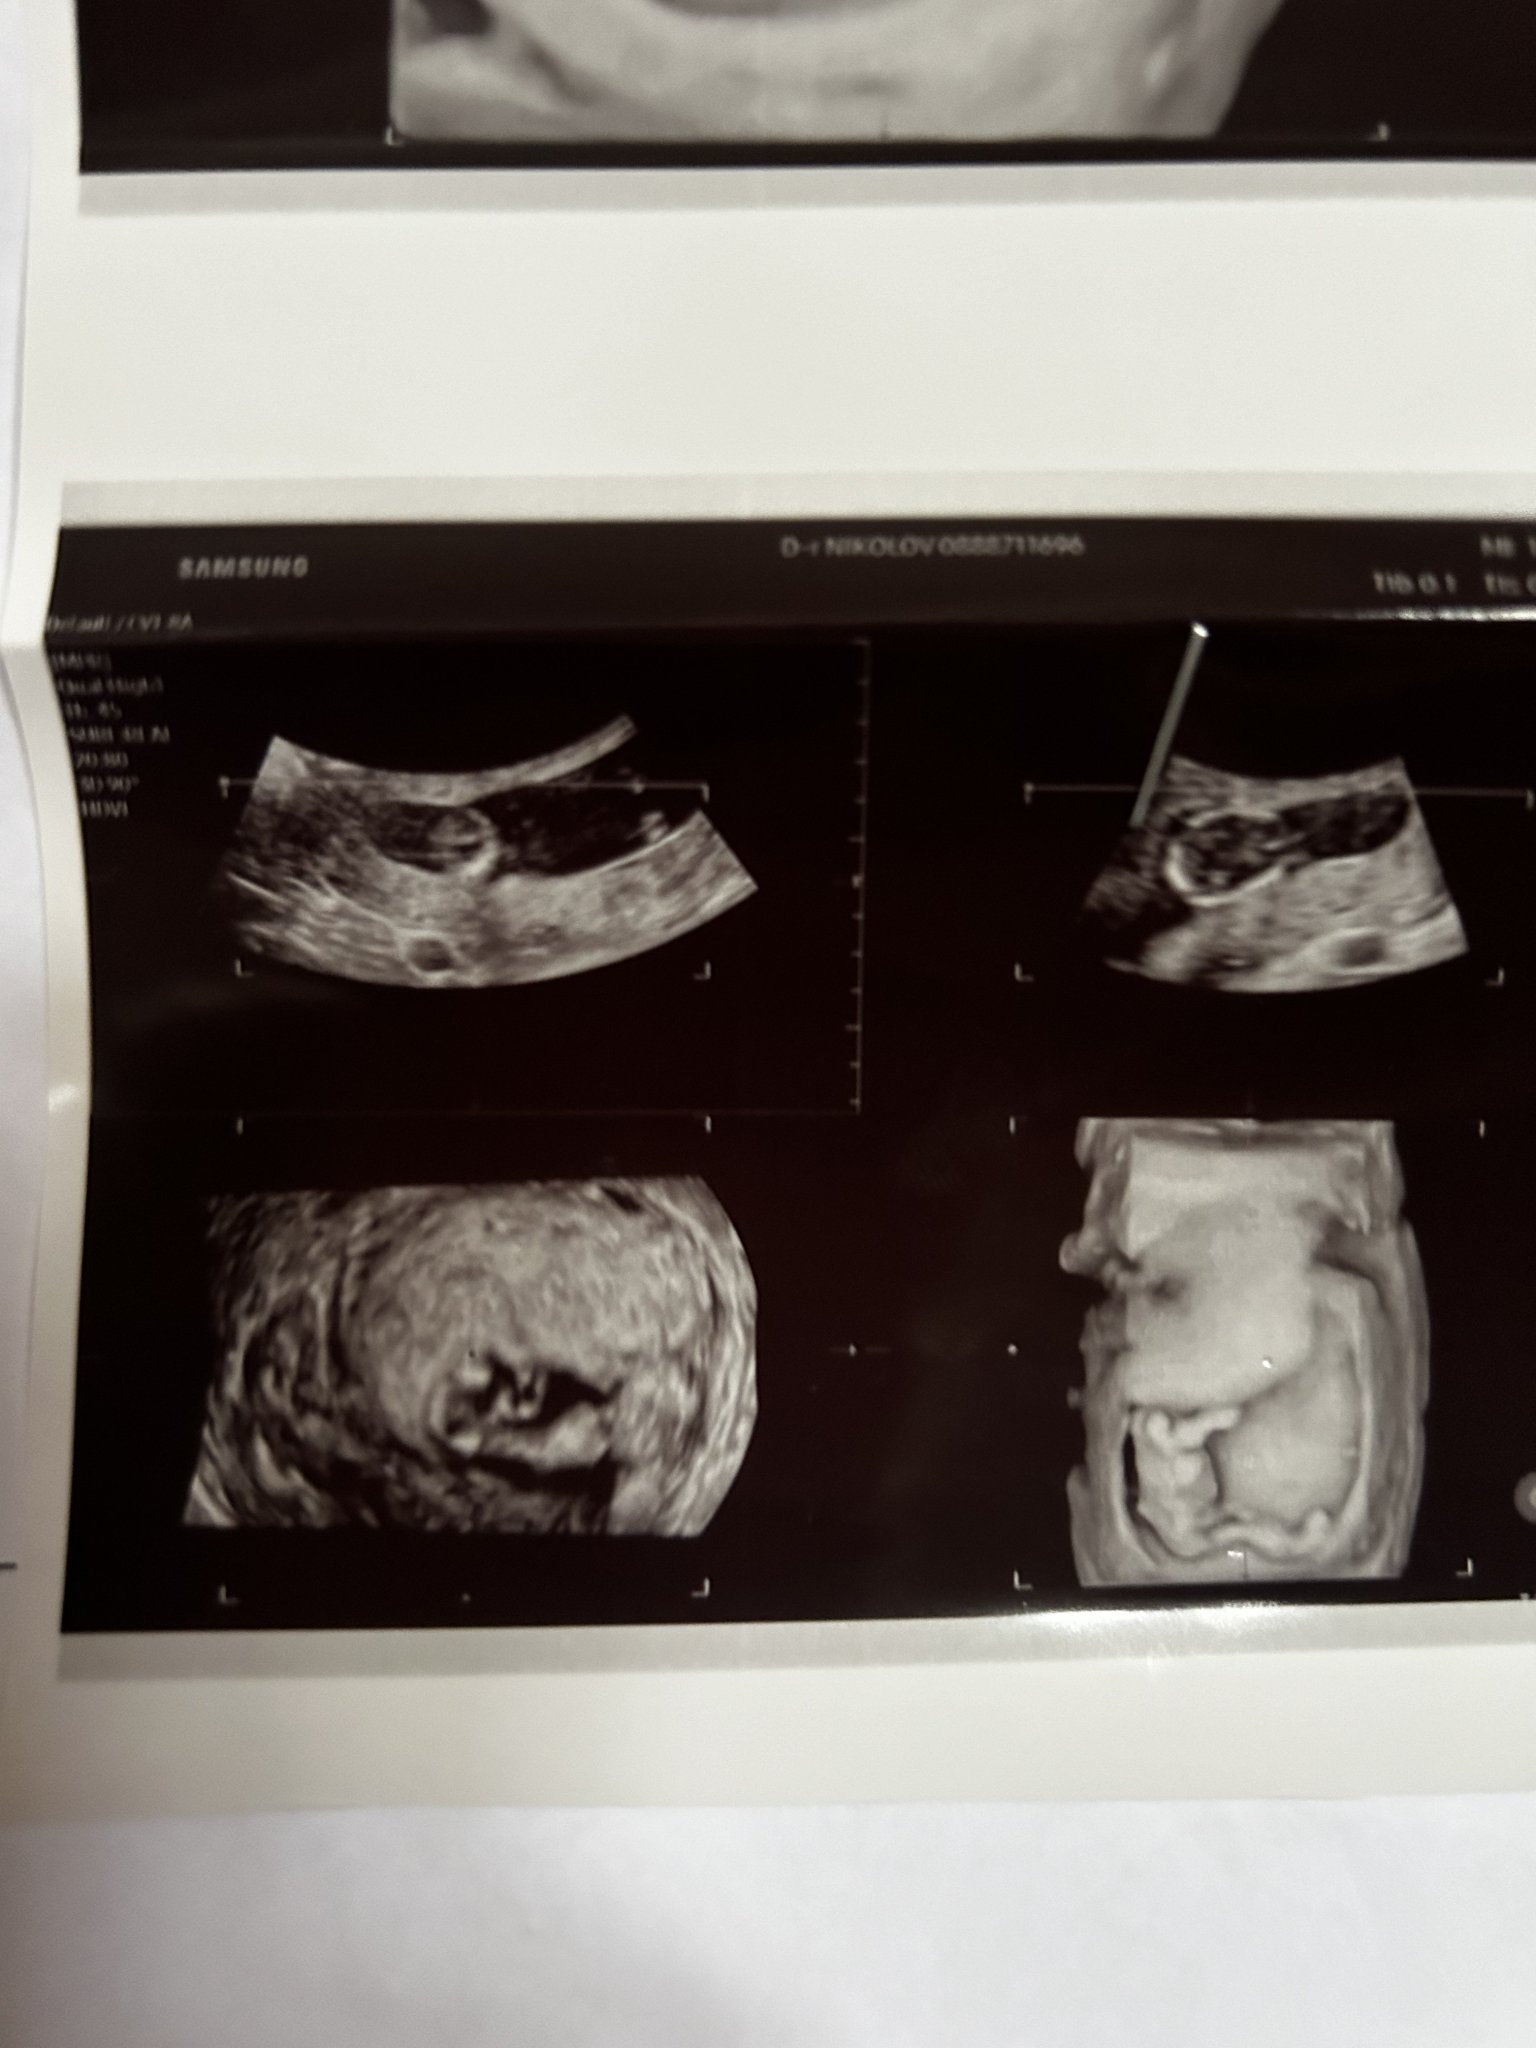

Здравейте. Вчера бях на преглед закъсняваше ми 13 дни нито правих някакви тестове. Вече имам спонтанен аборт миналата година и кюртаж

както и биохимична бременност.

Оказа се че съм бременна последната ми менструация беше 20.10 не знам какво да очаквам пак…опитвам се да съм спокойна а се и стряскам и плаша от най малкото.

Трябва да съм в 6-та гестационна седмица

6,22мм

Както се вижда има ембрион има и пулс...честито и ти пожелавам успех до финала...изследвай си прогестерона за всеки случай да видиш да не е нисък и ако не си е хубаво да направиш едно изследване за тромбофилия...